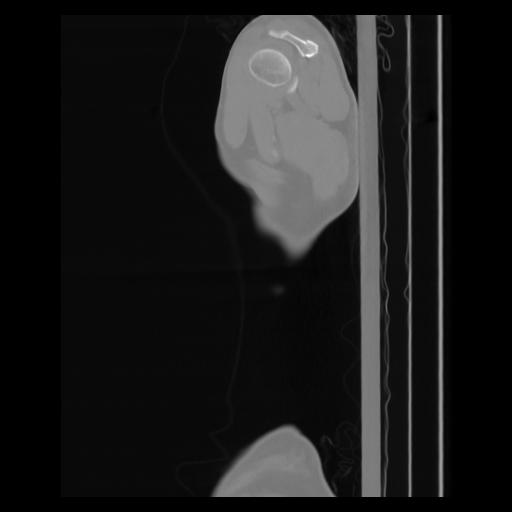

30 CUERPO,CE,Sagittal,3.000,CUERPO,Sagittal,